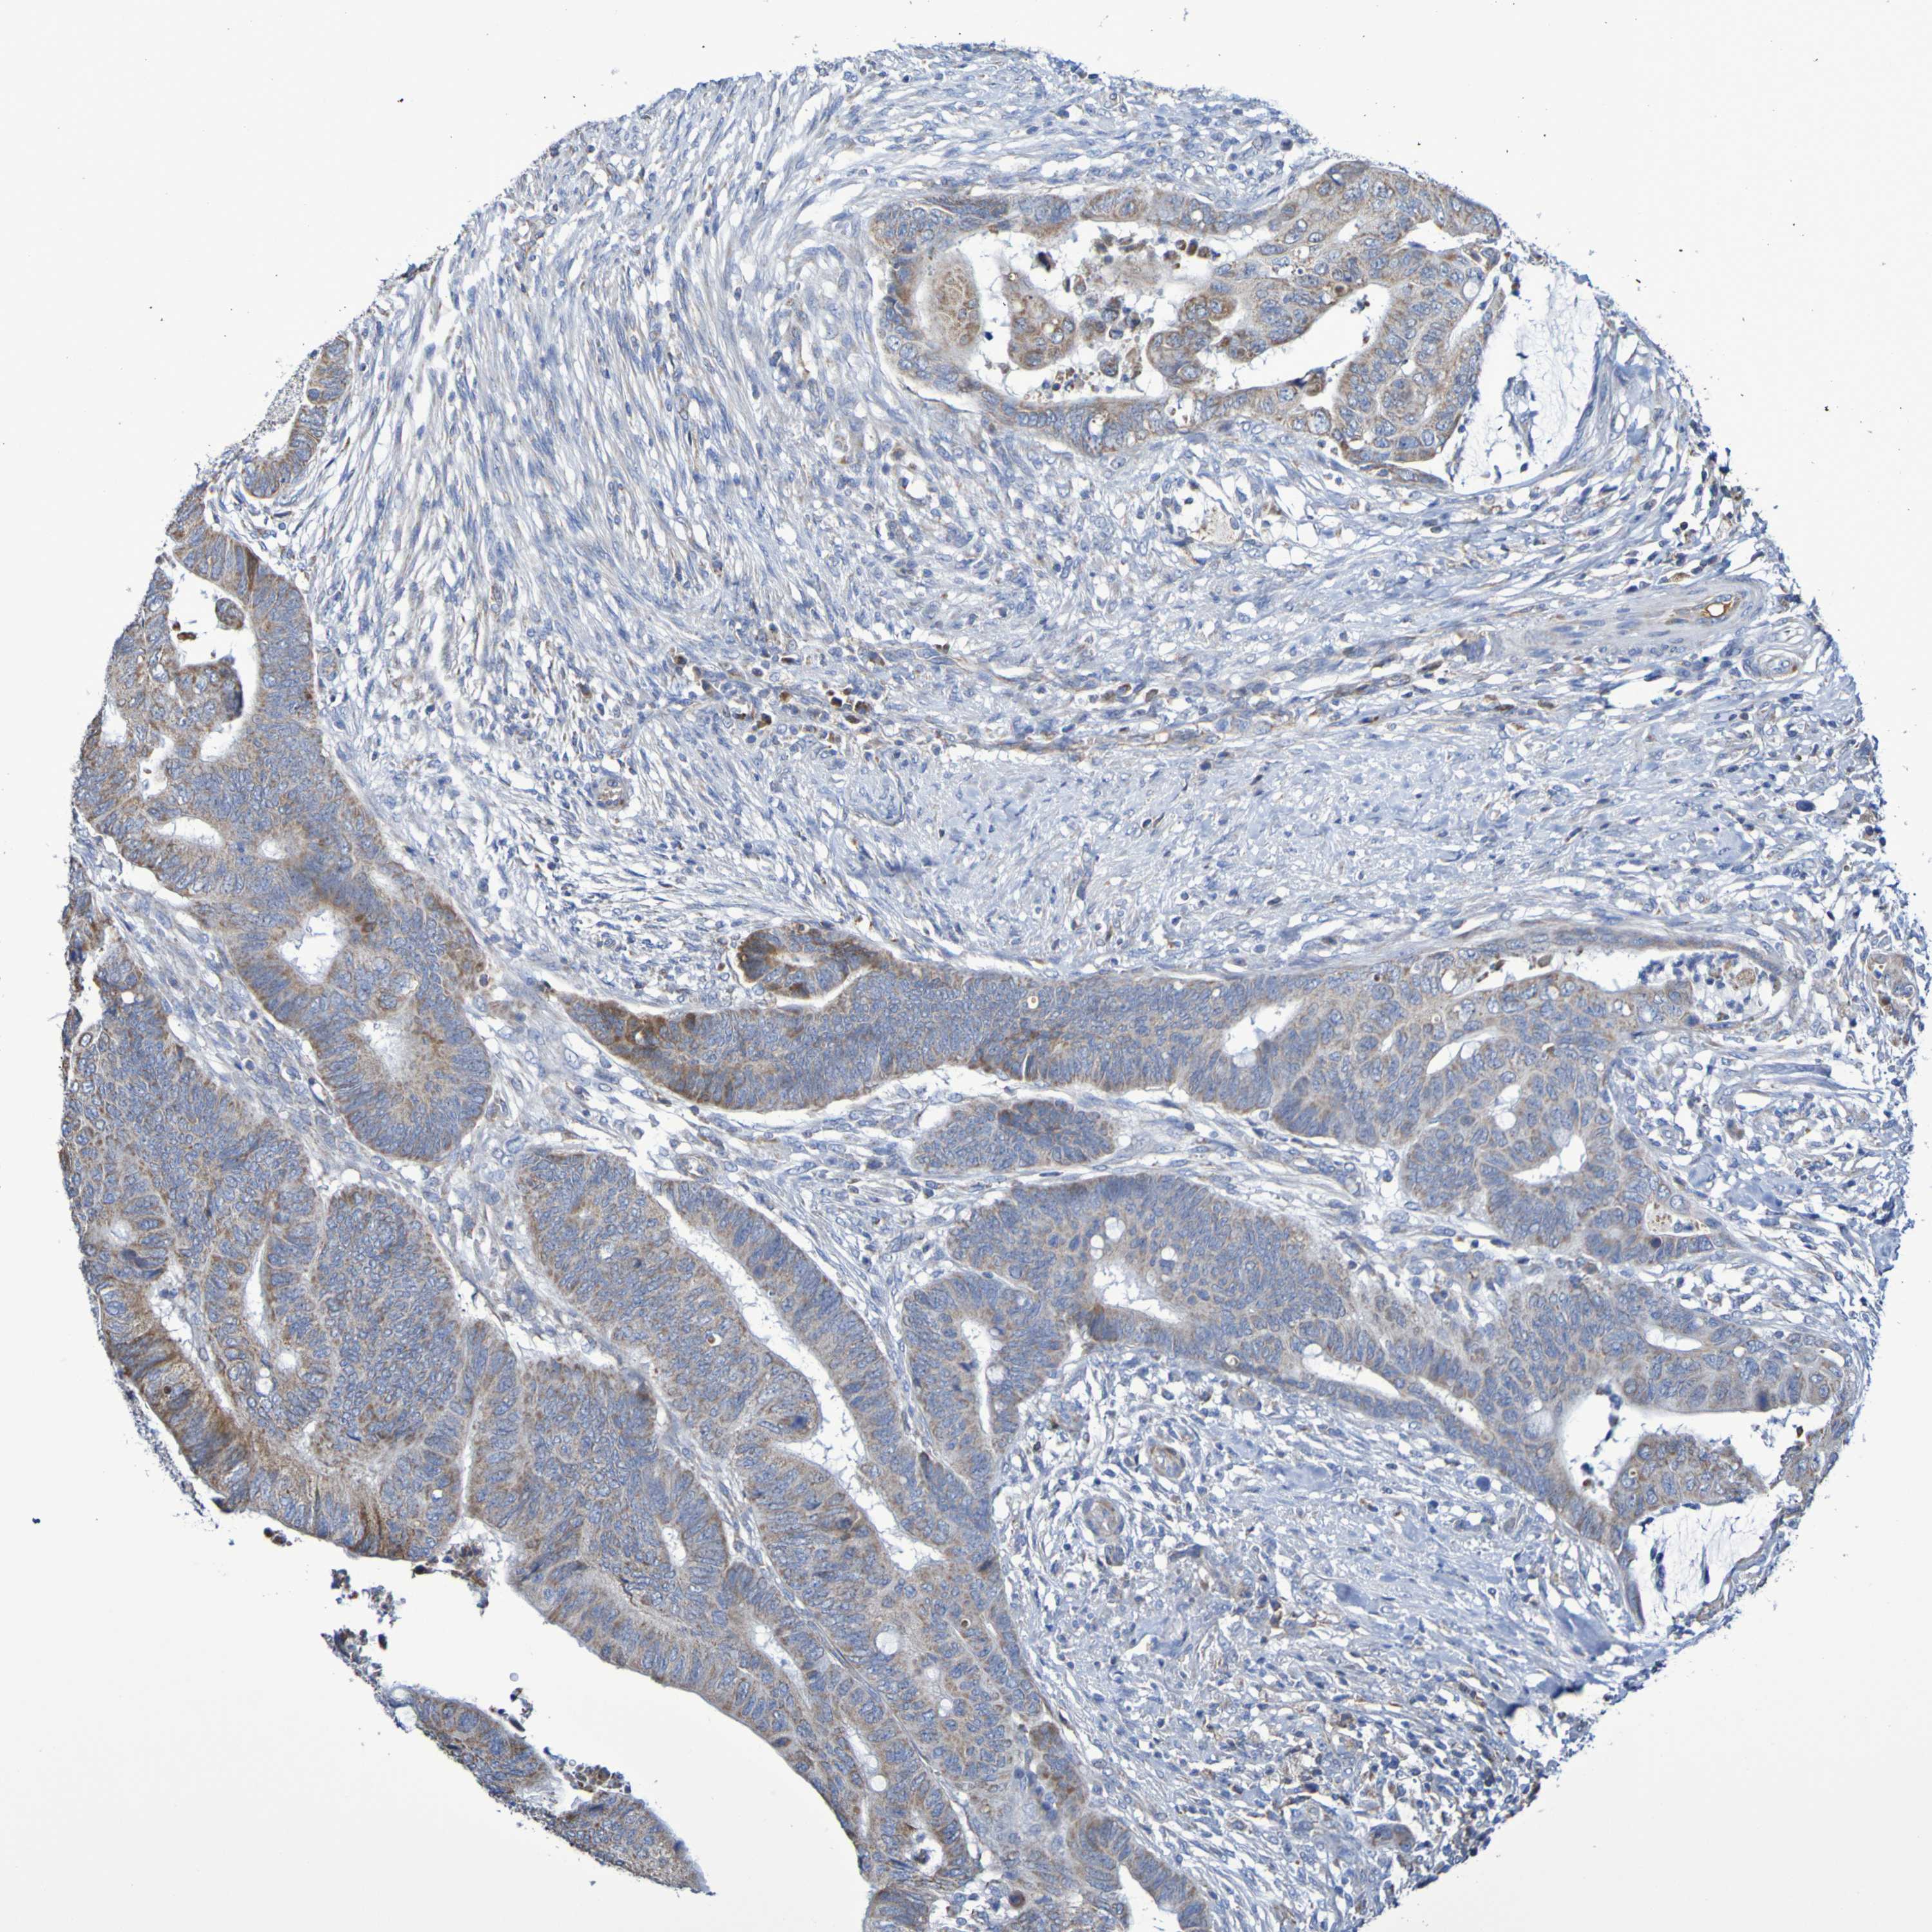

CANCER COLORECTAL CANCER Show tissue menu

Colorectal cancer

Human cancer

Colon adenocarcinoma